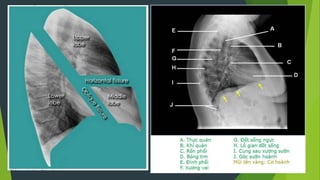

Giải phẫu hệ hô hấp

Tác dụng của phim X quang phổi nghiêng?

 Xác định vị trí của tổn thương theo thùy và phân thùy

 Chẩn đoán định hướng các khối u trung thất

 Khảo sát các vùng sau tim trái, sau vòm hoành hoặc trước rốn

phổi

 Chẩn đoán TDMP ít mà dịch khu trú ở góc sườn hoành sau không

nhìn rõ trên phim chụp thẳng